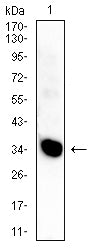

分类: 科研抗体货号: 32451别名: C9;DD1;DDH;DDH1;H-37;HBAB;MBAB;HAKRC;DD1/DD2;2-ALPHA-HSD;20-ALPHA-HSD应用: WB,IHC,FCM反应种属: Human,Mouse,Rabbit